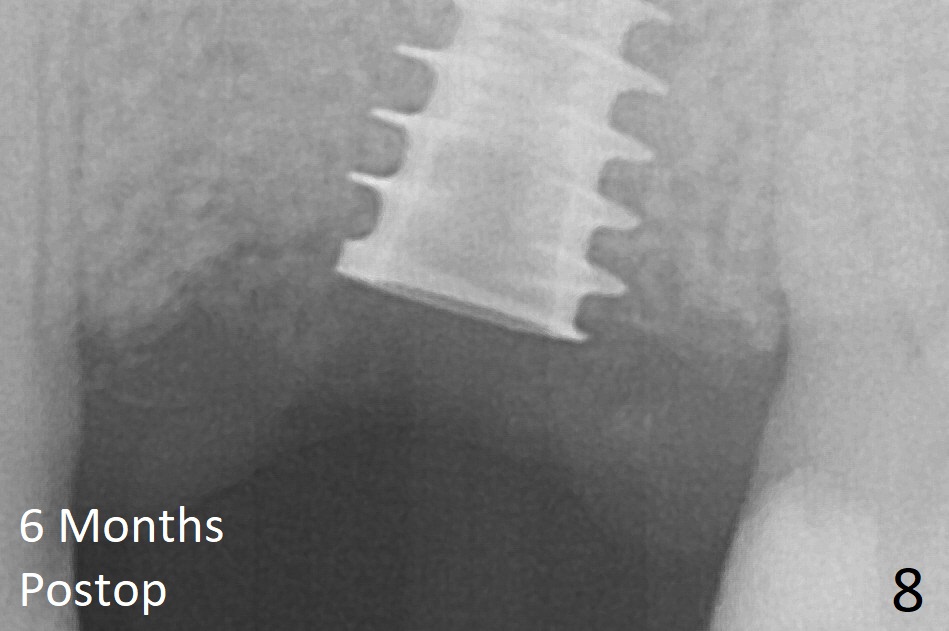

The implant is mobile 4 months postop (Fig.6). A 6x2 mm healing abutment is placed next. Although the implant remains mobile 6 months postop, the bone seems to have become denser around the implant (Fig.7-9). A healing screw is placed. When the bone height is limited (<7 mm), place a larger implant (>5.5 mm). The implant seems to have osteointegrated 8 months postop (Fig.10). Impression is taken following placing a 6.5x4(3) mm abutment. The patient reports pain after cementation, which is less when the abutment screw is loose (9.5 months postop, 2 weeks post cementation). CBCT taken after placement of a healing screw apparently shows loose bone mesial and distal to the implant (Fig.11 *). The implant trajectory is less favorable. It seems necessary to change to a large implant with more sold threads (Fig.12).